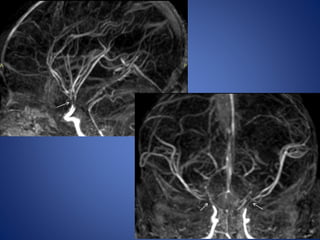

Moya Moya

• Chronic progressive arteriopathy of unknown cause and has

become one of the most common causes of pediatric stroke.

• Suzuki and Kodama classified the evolution of moyamoya disease

using angiographic findings to define six phases of the disease:

Stage 1- Narrowing of carotid fork.

Stage 2- Initiation of basal moyamoya.

Stage 3- Intensification of moyamoya

Stage 4- Minimization of moyamoya.

Stage 5- Reduction of moyamoya .

Stage 6- Disappearance of moyamoya.

• Stenosis/occlusion of the distal ICA

• moyamoya vessels with signal voids in the basal ganglia

• ischemia

• infarction

• atrophy, and ventriculomegaly.

• Small abnormal net-like vessels proliferate giving "puff of smoke"

appearance.

• Contrast-enhanced T1WI - marked leptomeningeal enhancement

along the cortical sulci (ivy sign).

often show contrast stagnating in slow-flowing collateral

vessels both in the brain parenchymal and over its surface.

MR imaging

5 yrs male child with history of left sided focal seizures with secondary generalization

5 yrs malechild with history of left sided focal seizures with secondary generalization